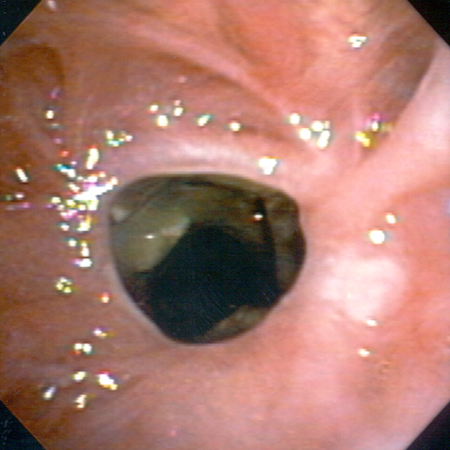

Обструкция нижних дыхательных путей: злокачественная обструкция правого бронха

Из коллекций Хосе Фернандо Сантакруза, дипломированного врача, члена Американской коллегии специалистов в области торакальной медицины, DAABIP, и Эрика Фолка, дипломированного врача, магистра наук; используется с разрешения